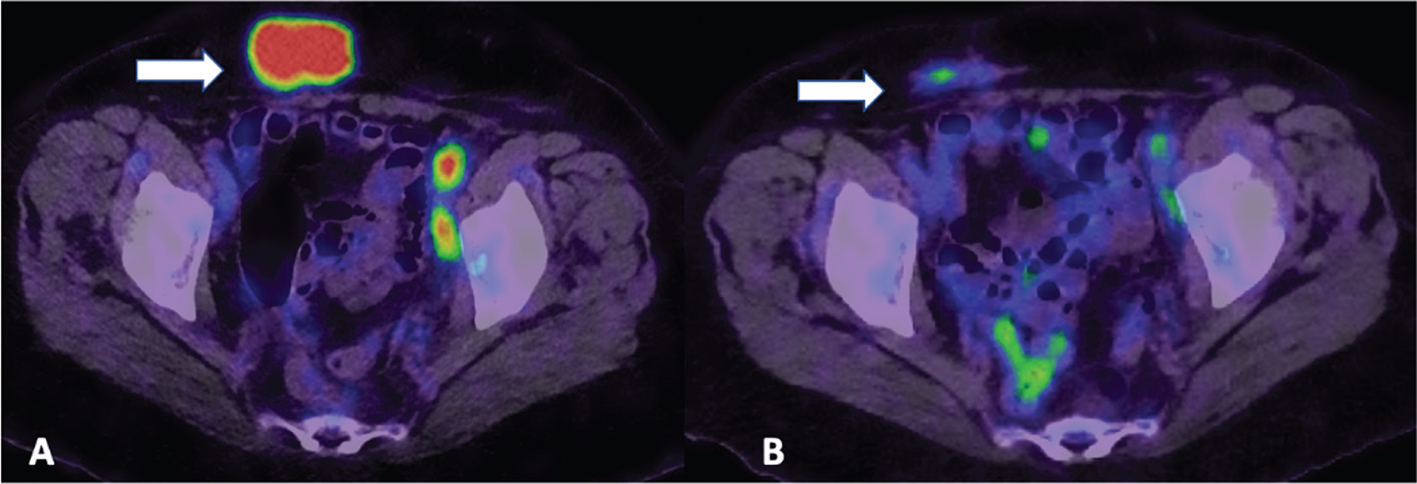

18F-FDG PET using EORTC or PERCIST criteria is useful in detecting early tumour response and precedes tumour markers response by 1 month and can also predict second-look surgery outcome and survival (31). FDG PET can predict the outcome after the first cycle of neoadjuvant chemotherapy early, a decrease of >20% in SUVmax after the first cycle of chemotherapy and >55% after the third cycle were found to correlate significantly with overall survival (32). FDG PET CT is superior to morphological imaging in assessing treatment response as molecular imaging with FDG PET identifies residual viable tumour whereas inflammatory lymph nodes or scar tissue may be misinterpreted as residual disease on morphological imaging (Figure 1).

Fig 1

Figure 1. Treatment response evaluation. 18F-FDG PET/CT images obtained from a 68-yr-old patient with recurrent ovarian carcinoma for assessment of treatment response. Image A demonstrates an intensely FDG-avid metastatic abdominal mass on pre-treatment FDG PET/CT, with significant post-treatment improvement noted on Image B.